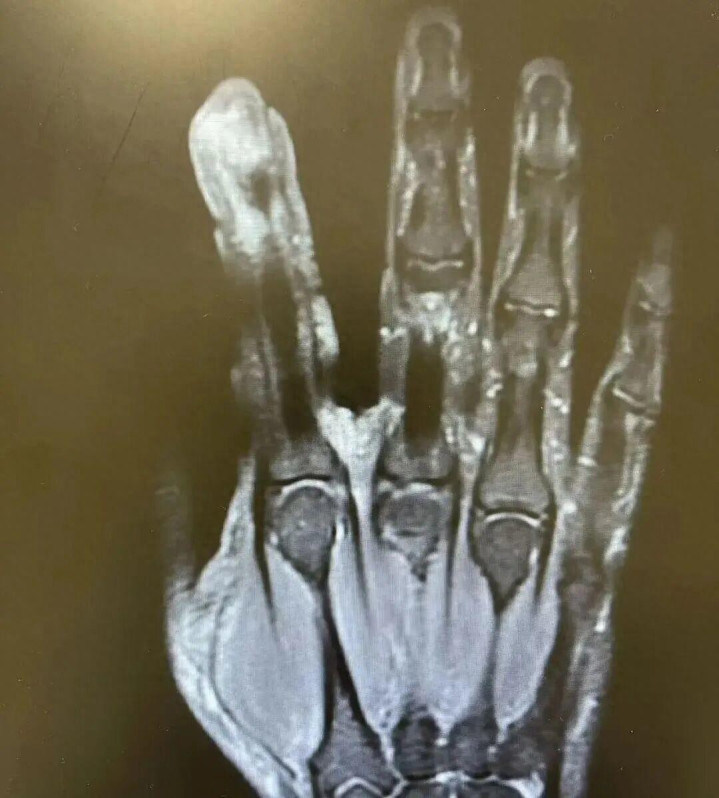

经查验,李老迈破溃的左手指尖严重感染,厌氧消化链球菌顺着阻扰处钻到骨头里,激勉了严重骨髓炎。医师热切手术,帮李老迈“刮掉”坏死的骨头碎屑,根除了坏死的肌肉与皮肤。

图源:健康广东